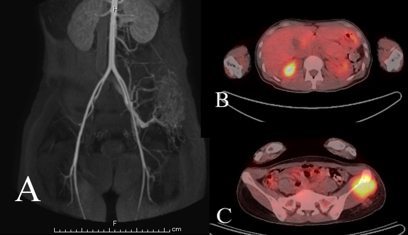

The case reported here is about a 30-year-old woman, who presented with a 6-month history of left buttock pain. She had no major past history. On physical examination, swelling and skin redness were observed on her left buttock. Further, an antero-posterior radiograph of the pelvis revealed the presence of osteolytic lesion in the left iliac crest (Figure 1A) and computed tomography (CT) revealed a destructive and moth-eaten appearance in the ilium as well as the presence of soft tissue mass on both sides of the bone (Figure 1B). Furthermore, magnetic resonance angiography (MRA) revealed diffuse hyper-vascularity in the lesion (Figure 2A), and axial non-enhanced T1-weighted magnetic resonance imaging (MRI) of the lesion revealed a homogeneous higher signal intensity than the adjacent muscle. On both T2-weighted image and short tau inversion recovery (STIR) images, the high signal intensity predominantly denoted the lesion, while the low signal intensity corresponded to the central portion and flow voids (Figure 3). Additionally, based on MRI, the tumor measured 48×63×73 mm. These radiological findings strongly suggested the presence of a malignant bone tumor, possibly Ewing sarcoma or lymphoma.

Figure 2: MRA image showing tumor hypervascularity in tumor of the left ilium (A). 18F-FDG PET-CT image demonstrating increased FDG uptakes in the right kidney (B) and left ilium (C). The SUVmax values are 8.1 (B) and 4.8 (C), respectively.

Osteolytic lesions, such as destructive or moth-eaten appearance in plain X-ray or CT images and soft-tissue masses in CT or MRI images, are the common radiological features in all ASPS cases [4],[5],[7],[8],[9],[10] (Table 1). These findings are common to primary malignant bone tumor, such as osteosarcoma, Ewing sarcoma, and lymphoma. However, the distinctive MRI features of ASPS are intermediate-high signal intensity in T1-weighted images and high signal intensity in T2-weighted images. In three of the six previously reported cases, signal voids and/or low signal intensity in the central necrosis were observed [5],[7]. These MRI findings are similar to that of soft tissue ASPS [11],[12].